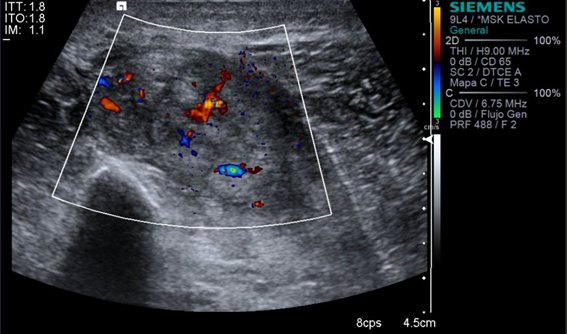

Eco Doppler